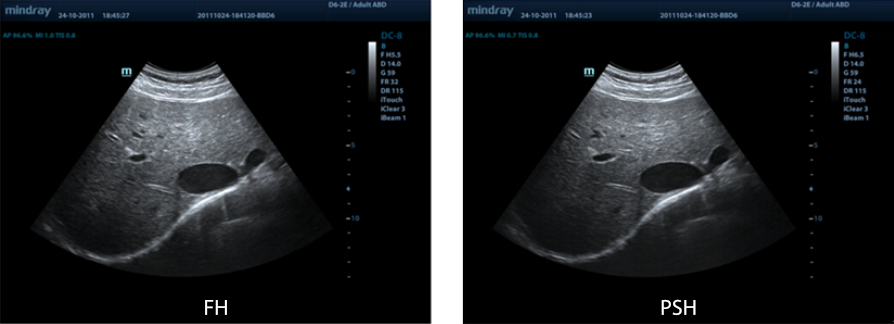

iBeam? (obrazowanie krzy?owe)

Funkcja ta pozwala wykorzystywa? skany wykonane pod r├│?nymi k?tami do stworzenia pojedynczego obrazu, co daje wzmocnienie rozdzielczo?ci, kontrastu i lepsz? wizualizacj?.

PSHI?(Phase Shift Harmonic - obrazowanie harmoniczne z przesuni?ciem fazy)

Funkcja obrazowania harmonicznego zapewnia lepsz? rozdzielczo?? i kontrasowo??, daj?c wyra?niejsze, bardziej klarowne obrazy o doskona?ej rozdzielczo?ci i mniejszym poziomie zak?óceń.